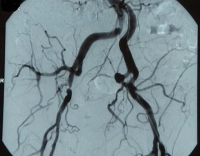

Gestão perioperatória - PTA da artéria ilíaca comum direita e da artéria ilíaca externa em DAOP estágio IIb

Exemplo de vídeo: TASC B, estenose de alto grau da A. iliaca externa e estenose de 50 % da A. iliaca communis à direita, clinicamente estágio IIb de DAOP de acordo com Fontaine → Indicação para reconstrução endovascular